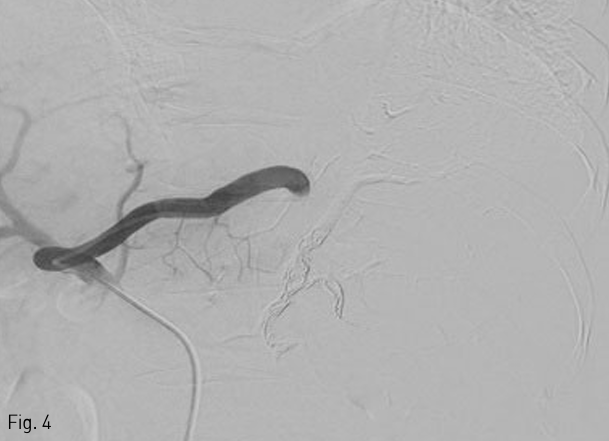

간경화와 비장비대 및 esophageal, paraesophageal, and gastric fundal varices가 복부 전산화단층촬영에서 확인되었다(Fig. 1).

Fig 1

Arterial phase of abdominal CT scan shows liver cirrhosis with marked splenomegaly and gastric fundal varix.